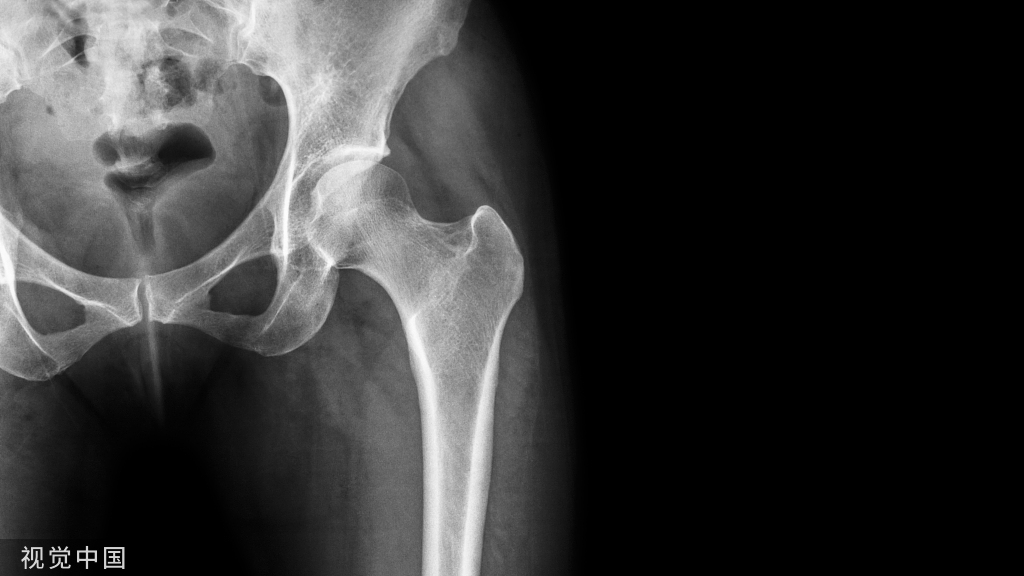

图2:三踝骨折患者,后踝未固定,术后6周取去下胫腓螺钉